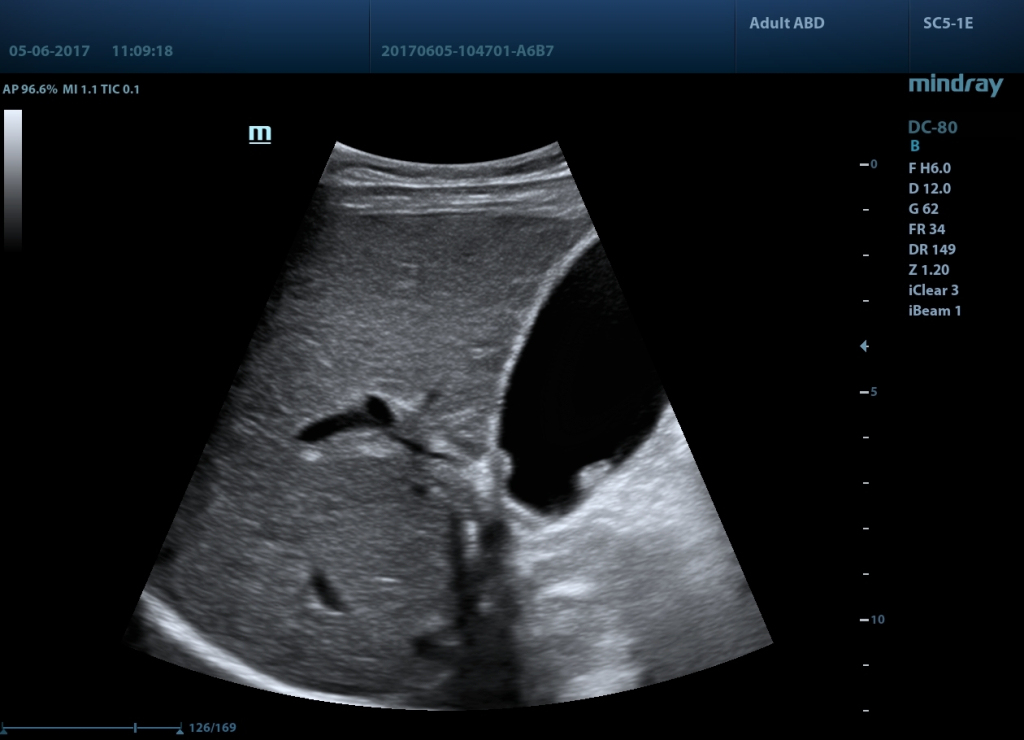

Галерея изображений: